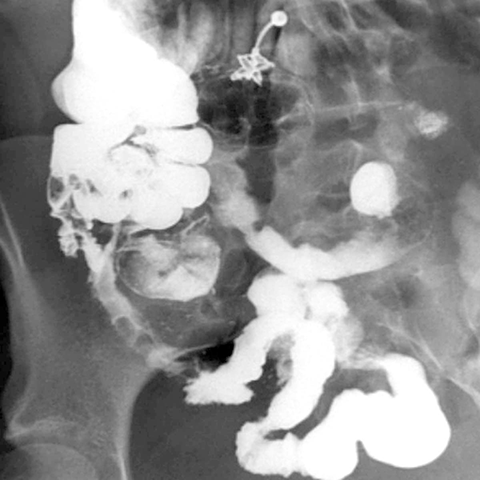

26 year-old female presents with chronic diarrhea, abdominal pain and weight loss. [1 of 2]